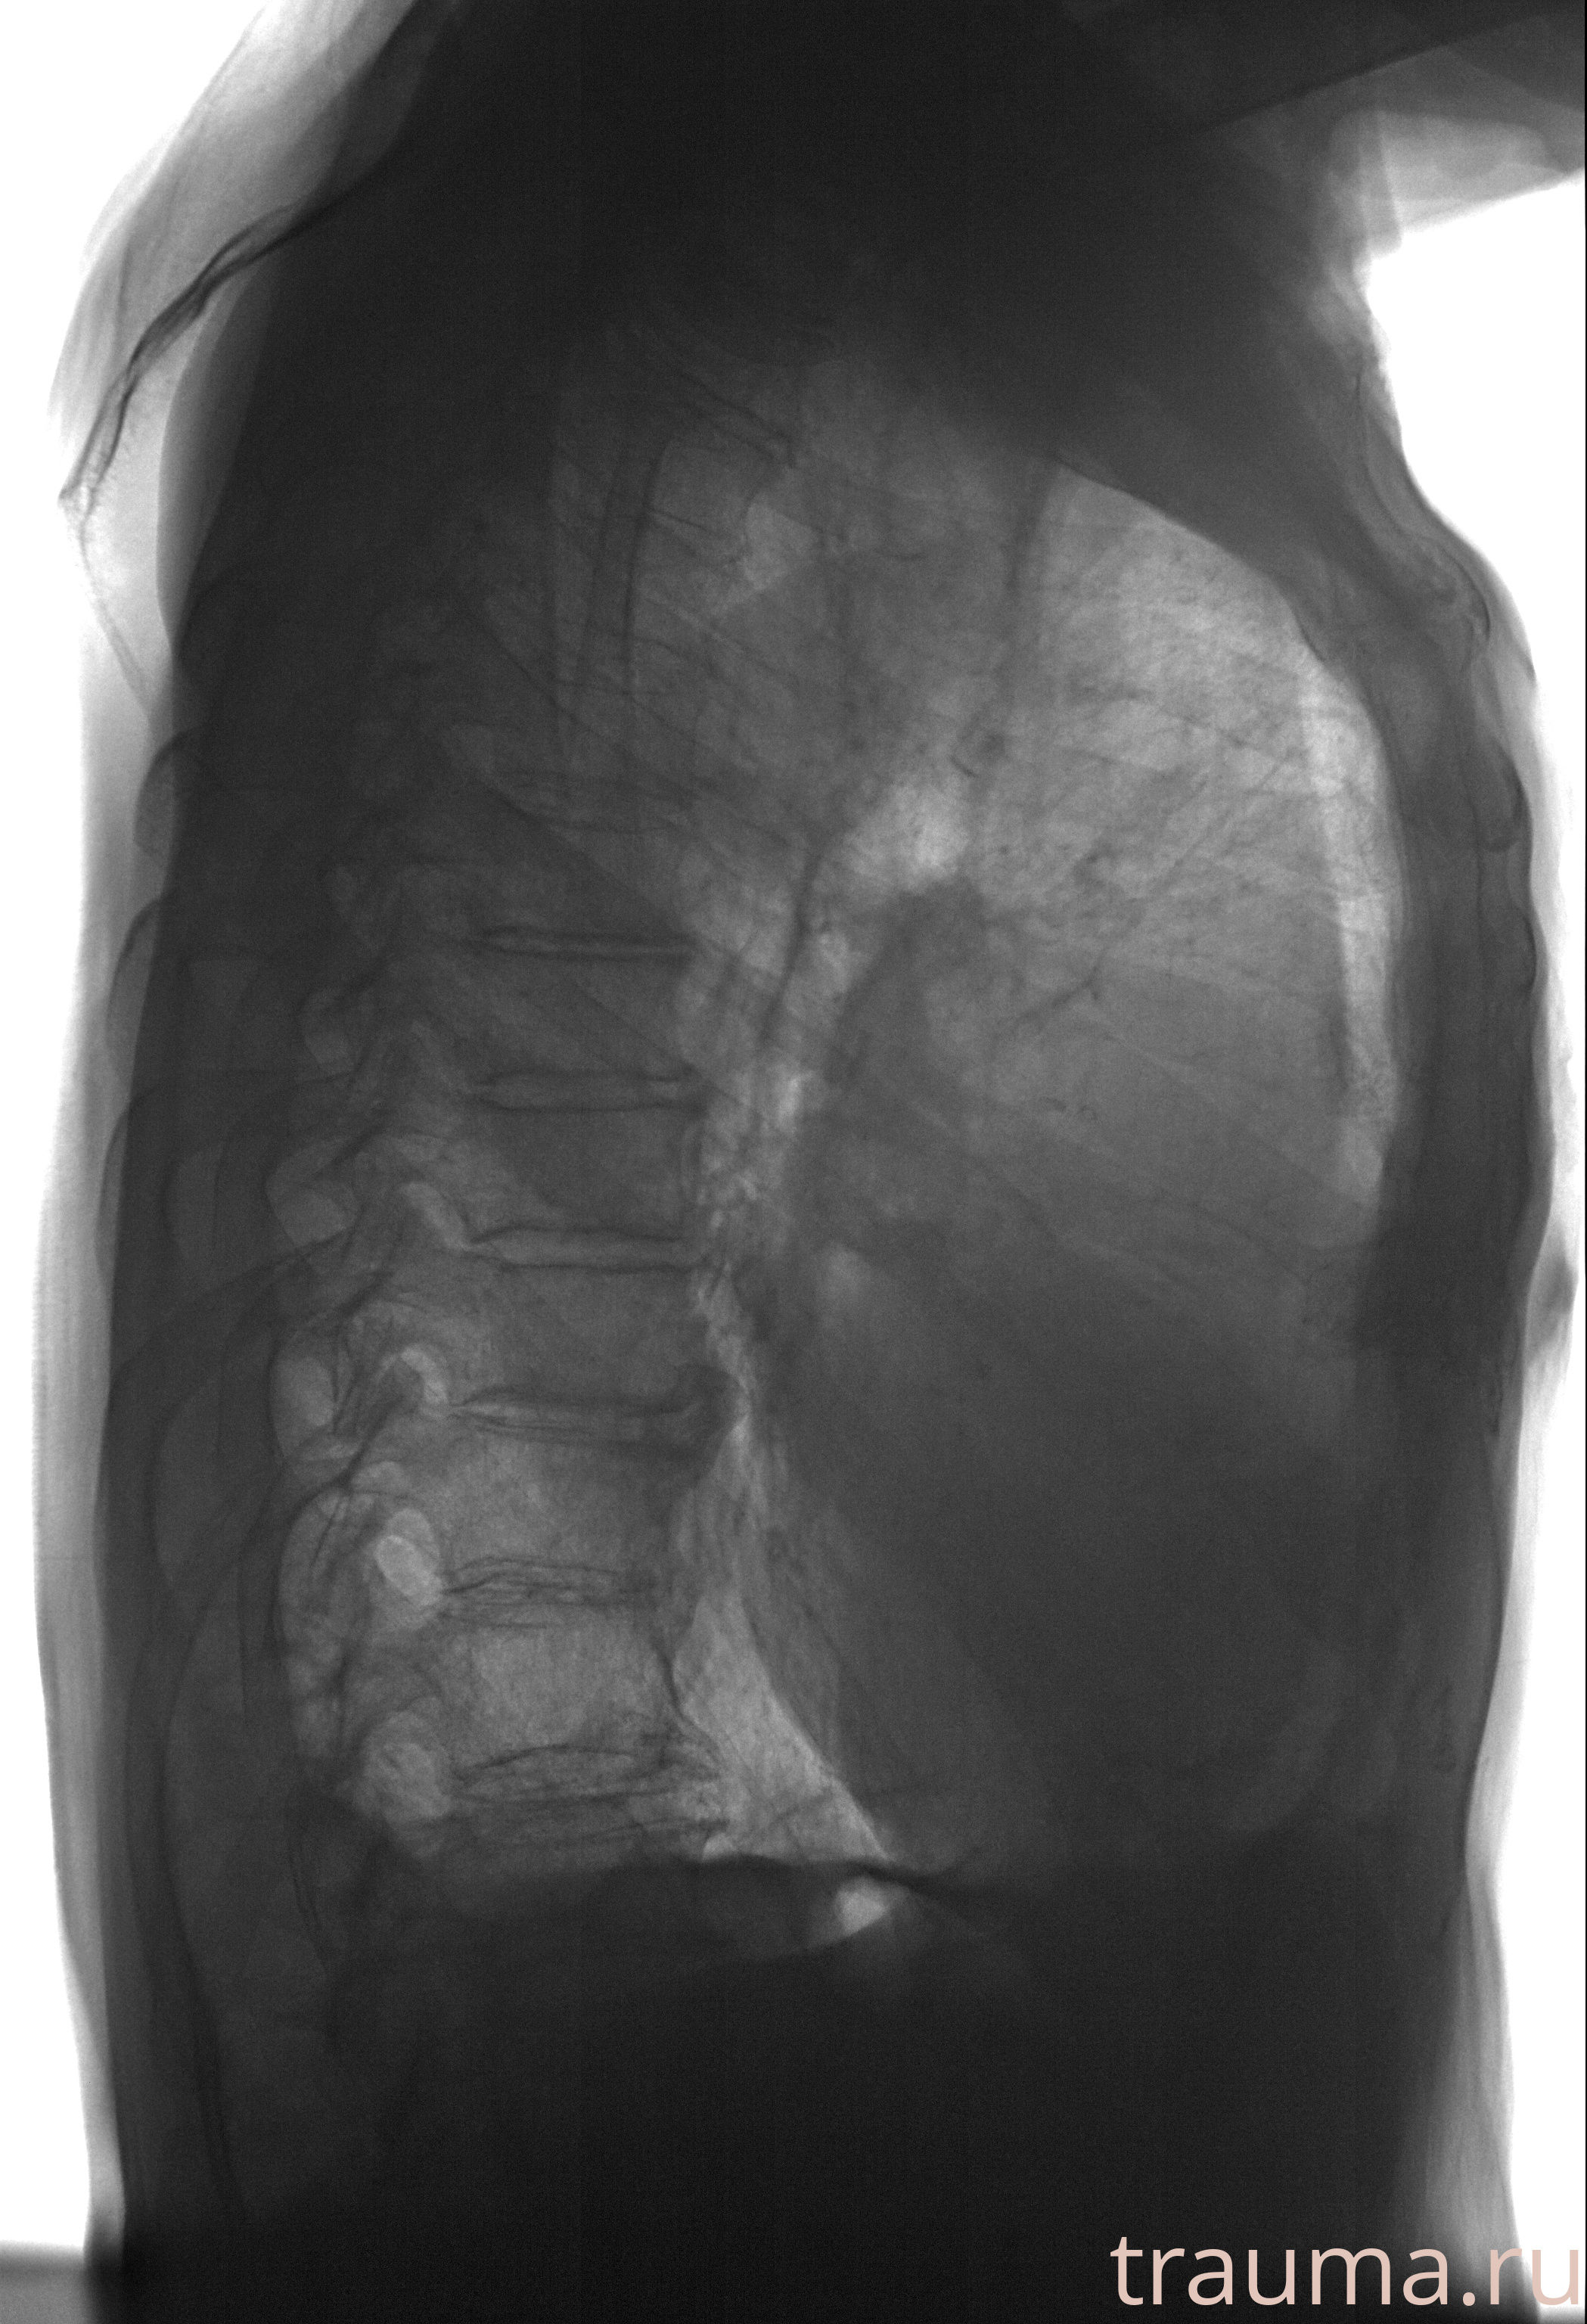

Рентген на дому: по вашему адресу приезжает врач-рентгенолог, травматолог-ортопед с мобильным рентгеновским аппаратом, проводит диагностику травмы или заболевания, делает необходимые рентгенограммы, дает рекомендации по дальнейшему лечению. Получить качественные снимки в домашних условиях возможно благодаря уникальной методике, разработанной МосРентген Центром для института  Склифосовского